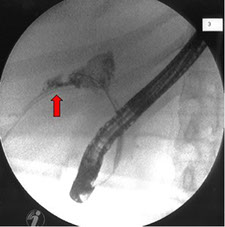

Fístula Biliar

La fístula biliar postraumática es el paso anormal del contenido líquido del tracto biliar hacia un órgano, cavidad o cuando se tiene un drenaje artificial hacia la superficie externa del abdomen.

Las fístulas biliares provenientes del conducto cístico, el conducto biliar común y los conductos de Luschka, responden bien con la descompresión del conducto biliar mediante la colocación endoscópica de una prótesis o una sonda nasobiliar con o sin esfinterotomia.

Las tasas de éxito para el cierre de las fístulas biliares en estos casos dependen del tamaño y la localización de la fuga, y van del 80% al 100%

Fuga Biliar

Las lesiones o fugas biliares ocurren posterior a la colecistectomía abierta o laparoscópica. La fuga biliar se trata mediante colangiopancreatografía retrógrada endoscópica (CPRE). La esfinterotomía y colocación de endoprótesis biliar disminuyen la presión del conducto biliar al duodeno, y promueven el flujo biliar transpapilar, con una respuesta del 70-90%.